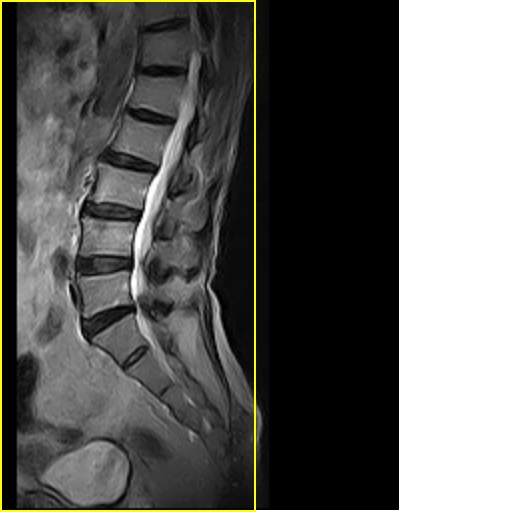

男,78岁,右下肢跛行两月.

腰间盘膨出、黄韧带肥厚、可疑先天性腰椎管狭窄。

退行性骨关节病:增生、椎间盘变性、膨出...

退行性病变:增生、椎间盘变性、膨出[l4-5、l5-s1 椎间盘膨出]

退行性骨关节病:增生、椎间盘变性、膨出..黄韧带肥厚.